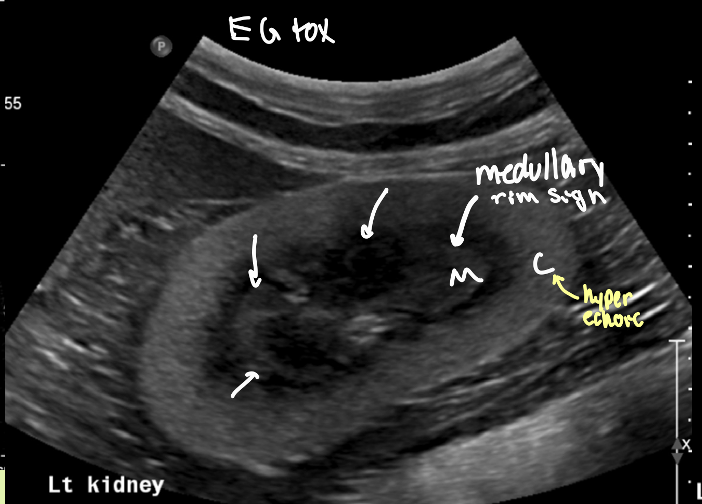

Toxic - ethylene glycol tox

is the medullary rim sign something to be worried about

no! can see in both normal small dogs and diseased kidneys